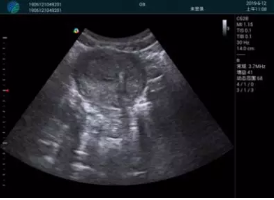

便攜超聲引導(dǎo)下人流術(shù)

病例一:

清晰顯示孕囊,通過軟件包計(jì)算孕齡7w+6d

M20實(shí)時(shí)引導(dǎo),術(shù)中清晰顯示孕囊被破壞和抽吸針的過程,清晰顯示吸引針

抽吸結(jié)束后縱切子宮,孕囊已被完全抽吸,未見明顯殘留

橫切子宮,發(fā)現(xiàn)右側(cè)宮腔靠近宮角處有少許脫模樣殘留

M20引導(dǎo)下,抽吸針找到右側(cè)宮角處再次清掃

二次抽吸后再次進(jìn)行超聲檢查,宮腔未見殘留,宮腔線清晰顯示

超聲引導(dǎo)下可視化人流是技術(shù)安全性的保障,一般對(duì)人流術(shù)設(shè)備預(yù)算不高,M20具備婦產(chǎn)科軟件包,且穿透力圖像質(zhì)量好,既滿足人流引導(dǎo)需要,也可用于床旁超聲的需求。